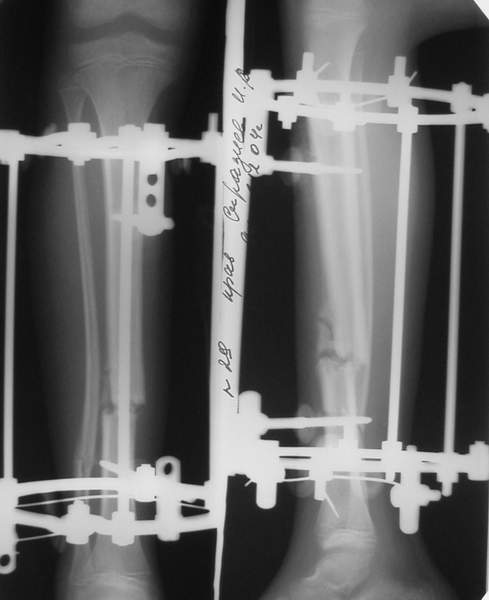

Под рукой прилагаемый пример. Как видите, "стриптиз-аппарат" (шутка проф. З.К.Башурова): 3 кольца-2 кольца-2 полукольца. В случае, который представил Евгений, характер повреждения позволил бы сразу использовать аппарат на основе 2 колец; в крайнем случае прокс. опора м.б. демонтирована сразу после репозиции.

В аттачтах №№ 1 и 2 - примеры, когда 2 кольца не позволили послеоперационно

исправить смещение фрагментов большеберцовой (по ширине и вальгусное).

А казалось бы (#2) - поиграй на штангах и все влетит.

1

1a

2

3a

3b

3c

В аттачте № 3 - один из примеров полукольцевого аппарат...

Это уже я баловался.

Итог? Работы больше (по времени и

интраоп "подгонке"), срастается также, а особого преимущества по сравнению с

"чиста" кольцевым (вес, удобство ношения и пр.) - я, по крайней мере,

не нашел.

Теперь не балуюсь.